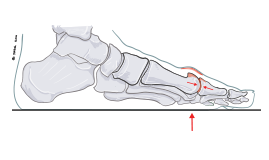

Hallux rigidus

Hallux rigidus innebär att artros, dvs minskad mängd brosk på ledytor, föreligger i stortåns grundled och orsakar stelhet, belastningssmärta och benpålagring i leden.

Artrosen kan komma av sig självt men kan även vara en följd av tidigare skelettskada, gikt eller reumatoid artrit.

Efter att man provat icke-kirurgiska behandlingsalternativ med rullsula och skoinlägg kan ibland operation bli aktuell.

Den kirurgiska behandlingen anpassas till vilka besvär som är dominerande. Man kan exempelvis ofta inledningsvis nöja sig med att avlägsna benpålagringarna när de ger besvär i form av skav och stelhet.

Har man svår värk och stelhet kan istället steloperation krävas för att uppnå bästa resultat.